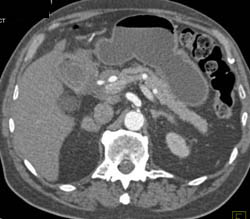

Chronic Pancreatitis